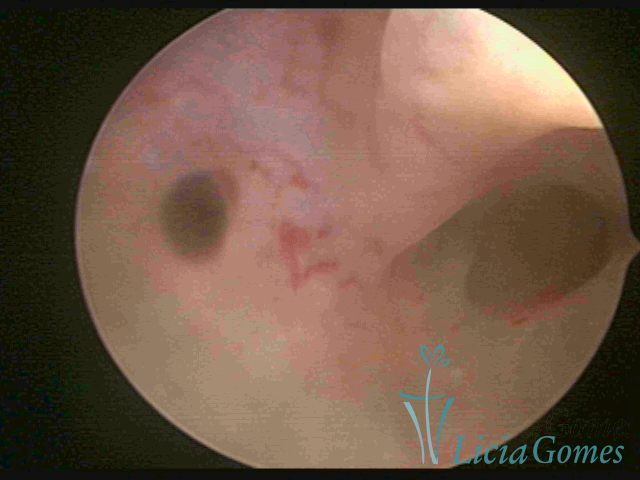

ADENOMYOSIS

The presence of endometrial tissue on the muscular layer of the uterus.

Video hysteroscopy allows diagnosing the lesions next to the superficial myometrial layers next to the endometrium, allowing the view of in situ, purplish, or chocolate brown lesions.